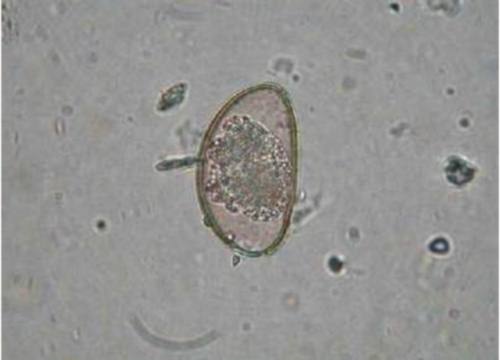

الصفات المورفولوجيه( الظاهريه ):

الأوأوسيست Oocyst والتى تعرف بالبيض المتحوصل، حوالى 4*6 ميكرون، وتحتوى على أربع كائنات بوغيه ليس لها غلاف خارجى Sporozoites وهى التى تسبب الإصابه .

الطور المعدى : هو البيض المتحوصل Oocyst .

طريقه العدوى :عن طريق إبتلاع البيض المتحوصل Oocyst مع الطعام أو الشراب، أو من خلال البراز أو الأيادى الملوثه المحمله بالبيض المتحوصل .

دوره الحياه :

بعدما يبتلع الإنسان البيض المتحوصل Oocyst تخرج الحيوانات أو الكائنات البوغيه Sporozoites ثم تُغْمِد فى الحواف الهدبيه لخلايا الأمعاء الطلآئيه، بينما تبدأ هذه الكائنات البوغيه فى الإنقسام تبدأ دوره التكاثر الإنفلاقى ( التشققى ) Schizogonyواتنلسل المشيجى Gametogony وذلك بنهايه تكوين البيض المتحوصل والذى يمر مع البراز .

إسم المــرض : الكريبتوسبوريديوسيس Cryptosporidiosis .

أعراض المرض :إلتهاب حاد محدود ذاتياً للمعده والأمعاء، وعنما يكون الشخص المصاب ذات جهاز مناعى غير نشط يؤدى المرض إلى إسهال حاد ومميت، ويسبب المرض أيضاً غثيان، فقدان الشهيه، التقلص المعوى، فقدان الوزن ودرجه حراره الجسم .

من الملاحظ أن مكمن الخطوره بهذا الطفيل هى الكائنات البوغيه والتى ليس لها غلاف خارجى.لذلك قال الدكتور دوبت وآخرون(1995) أن الطور المعدى الذى ينتقل يكون عن طريق شيئين :

اتصال الحيوان بالشخص أو العكس، اتصال شخص بشخص حامل للمرض . بالتالى تنتقل العدوى من مجرد نسبه صغيره إلى نسبه كبيره نوعاً ما .

عثر على بعض الأشخاص المصابين بطفيل الكريبتوسبيريديم ببلده رحوفوت بإسرائيل، وأكدت الدراسه أن العدوى كانت عن طريق الأوزاغ المنزليه والتى تعرف بإسم هيميداكتيلس Hemidactylus turcicus، والتى تم عزل الطفيل من القناة الهضمية الأمامية . وتم التعرف على الطفيل وأبعاده بالميكرسكوب الإلكترونى والذى وضح الكائنات البوغيه Sporozoite بالبيض المتحوصل Oocyst والتى تكون السبب الرئيسى فى الإصابه .

أكدت الأكاديميه على وجود العديد من البيض المتحوصل Oocyst للكريبتوسبوريديم، والتى تم التعرف عليه من عزل البراز وفحصه للعديد من الأوزاغ التابعه لشعبه الإبيكومبلكسا Apicomplexa، وقال الدكتور براونستين وآخرون عام 1977، والدكتوركرانفيلد 1994 أن الإصابه اكتشفت مراراً وتكراراً فى الغشاء المخاطى المعوى، وتم إكتشاف إصابه العديد من الأوزاغ بأنواع عديده من طفيل الكريبتوسوريديم، وتم إنتشار الإصابه للأسر والأماكن المحليه، وذلك بنوع يسمى كريبتوسبوريديم سايروفيلآم C. saurophilum، وقد وصف المربين التجاريين للأوزاغ بتفشى هذه العدوى الطفيليه، والتى كانت ظاهره على الأوزاغ من السمات المورفولوجيه .